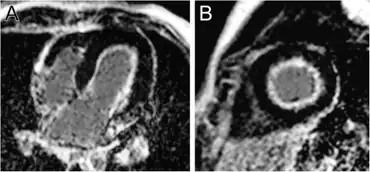

Developments in echocardiography, both the technology of the machines and the skill of the operators, have made it no longer necessary to see the endocardium at autopsy. EFE can now be found non-invasively by the recording of increased endocardial echos. Fetal echocardiography has shown that EFE can begin to accumulate as early as 14 weeks of gestation, and increase with incredible rapidity[15] and even that it can be reversed if the stress can be removed early in fetal life.[16]